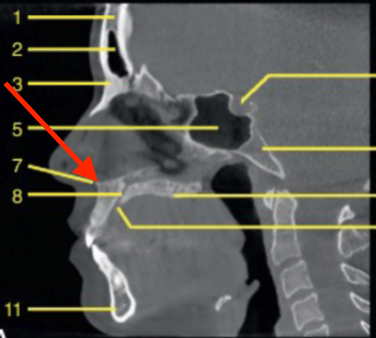

sagittal

what plane is this

what is the structure indicated by the arrow

identify the structure

what is 43

what is 52

identify 5

glenoid fossa

articular eminence

styloid process

mastoid process

mastoid air cells

external auditory canal

maxillary tuberosity

hard palate

nasopharynx

oropharynx

soft palate

tongue

palatine tonsils

epiglottis

C1

lateral pterygoid plate

pterygopalatine fossa

hyoid

sella turcica